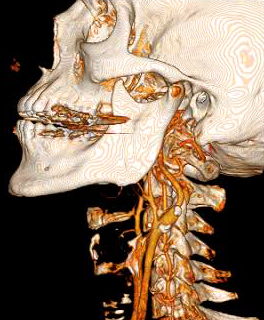

CTA of the Head and Neck image A for Radiology

How it works: CT angiography (CTA) evaluates the major vessels of the head, neck or both. An iodine based contrast agent is rapidly injected through an IV placed in a vein, usually in the arm. A CT scan uses x-rays to acquired images as the contrast bolus passes through the arteries. The data can then be reviewed in multiple planes, and 3 dimensional images can also be created for review.

Equipment: Most commonly, a 64 channel Philips CT scanner is used, however, in some situations a 16 or 256 channel CT scanner may be used. OHSU is an ACR accredited CT facility.

Benefits: CT angiography is a fast and minimally invasive method of evaluating vessels for abnormalities such as narrowing, blockage, aneurysms, and other vascular malformations.

CTA of the Head and Neck image B for Radiology